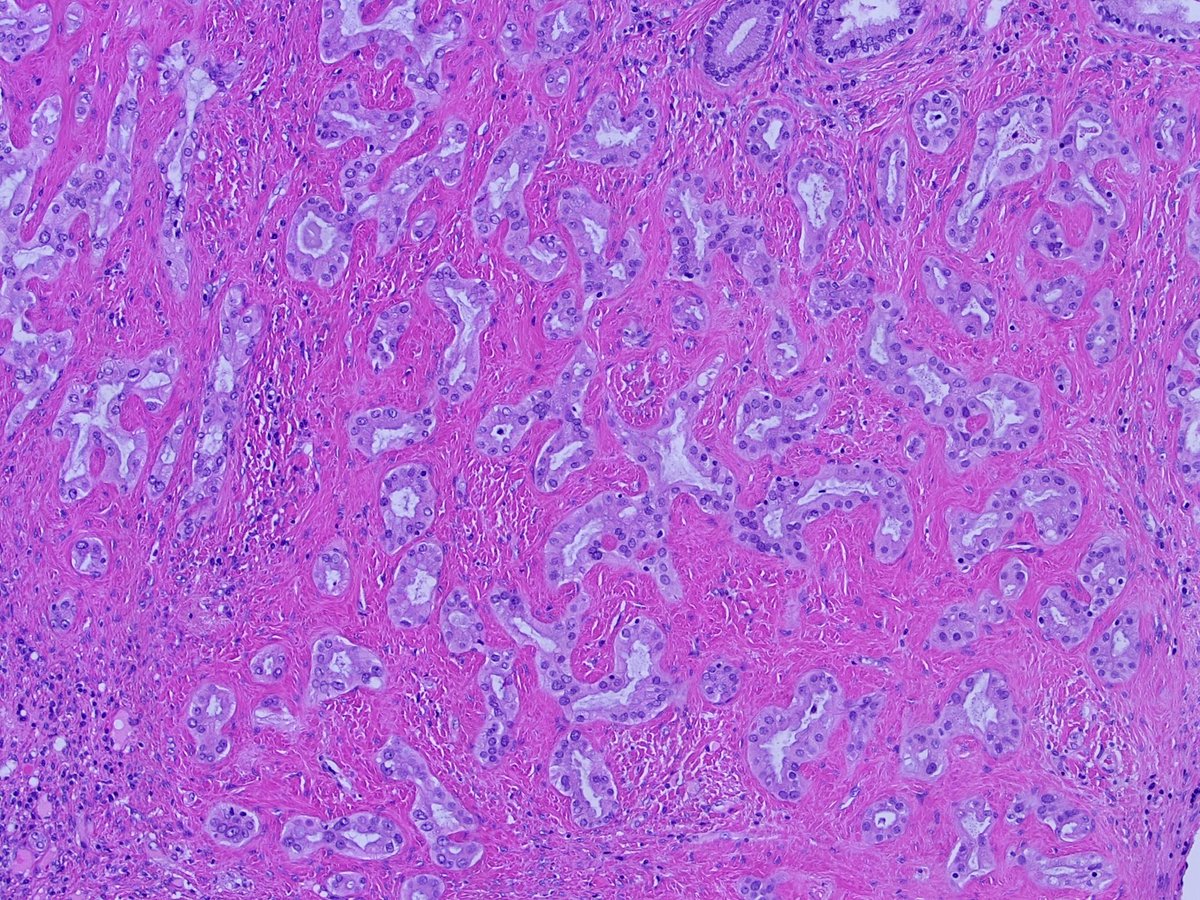

50 year old man; liver wedge resection. History of indeterminate pancreas lesion by imaging (chronic pancreatitis vs mass).

Diagnosis?

Discussion: I felt this was a nice case of bile duct adenoma. Some annotated images are posted below.